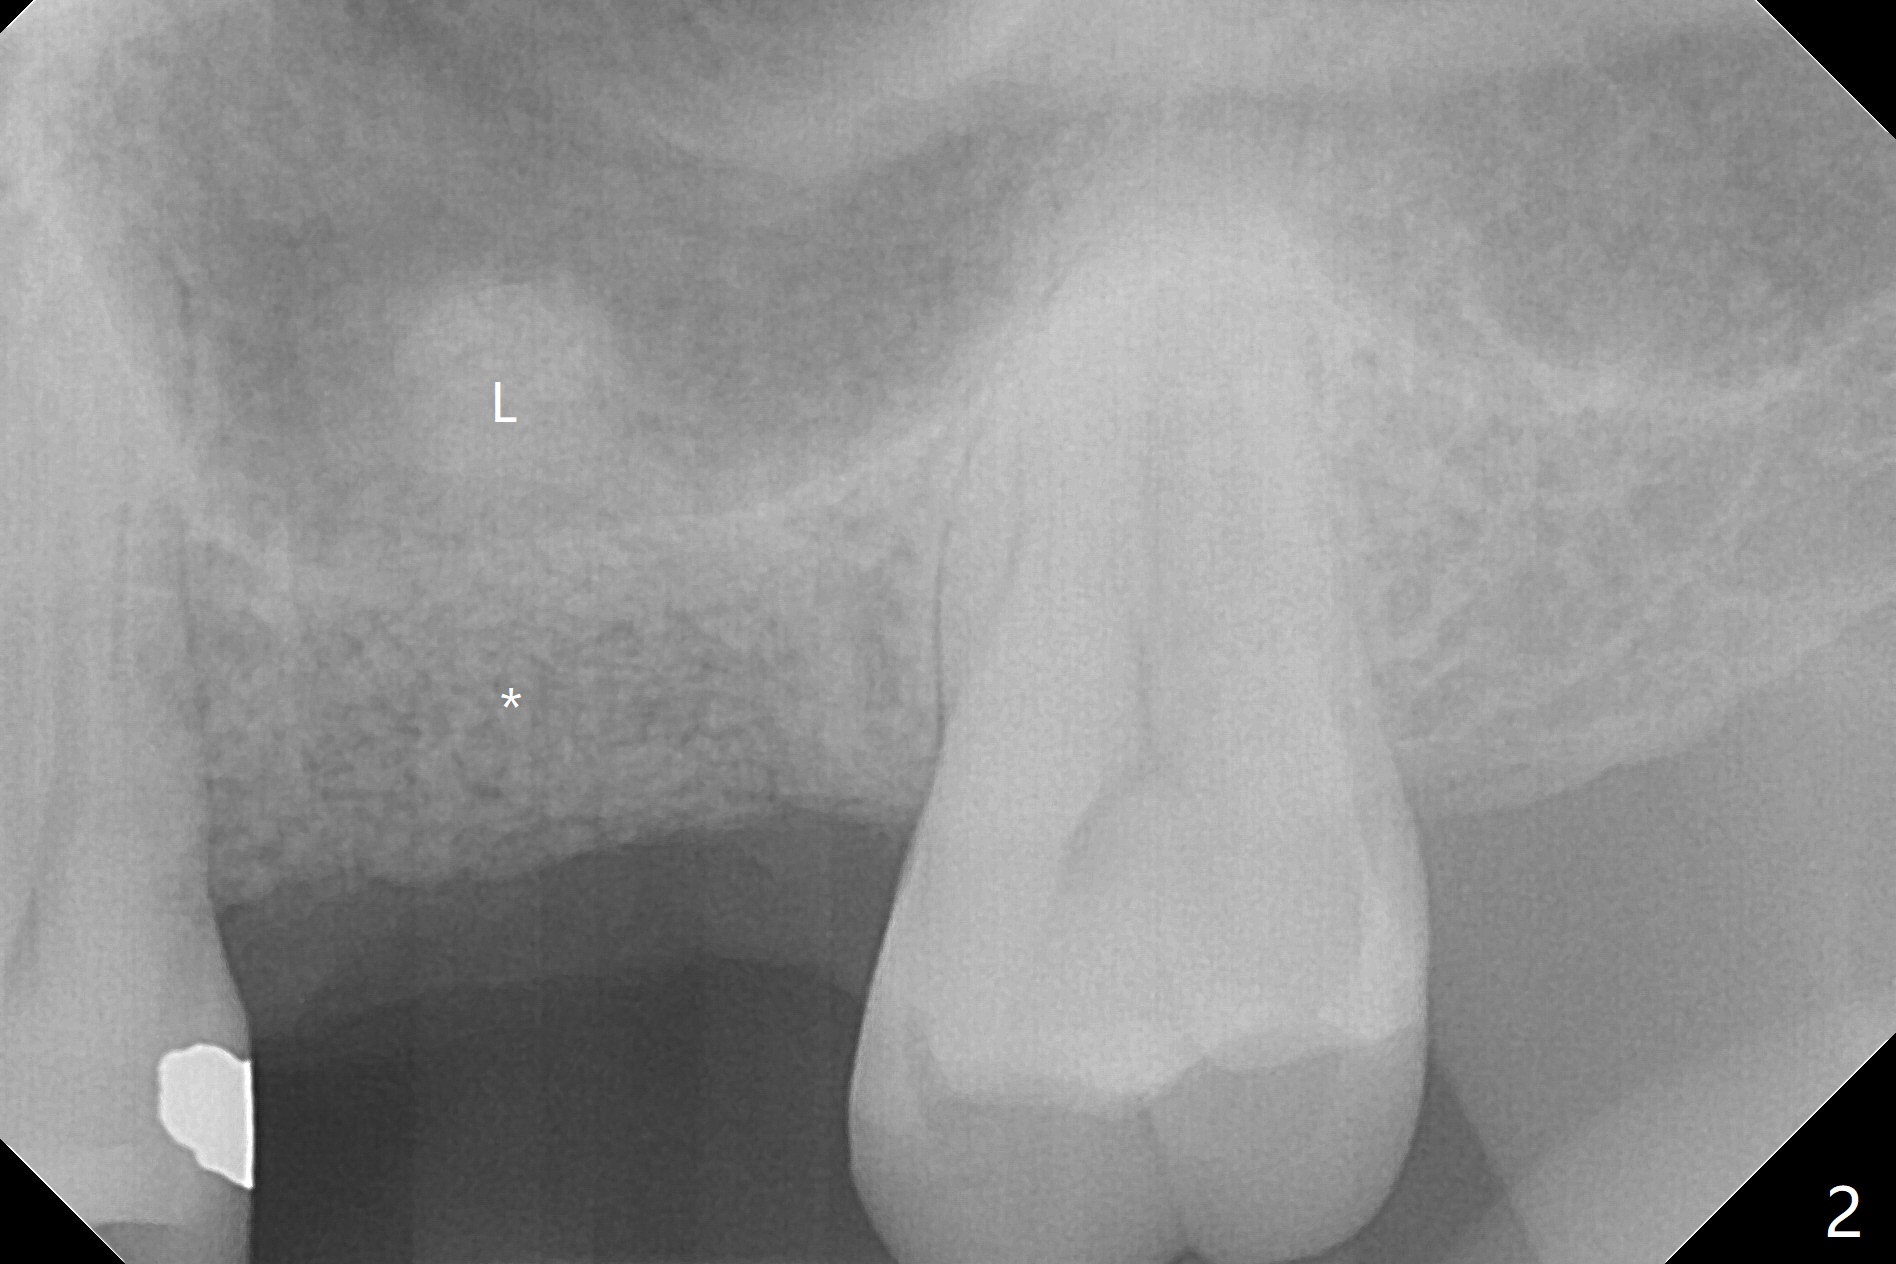

When the crown and abutment at #14 are removed, the implant is found to be shallowly placed. Upon incision, the implant threads are exposed circumferentially and coronal to the buccal crest (Fig.1 *). It seems to be difficult to expect bone regeneration post bone graft. The implant (6.4x6 mm) is removed with a 7/8 mm trephine bur, followed by sticky allograft (Fig.2 *), PRF membrane and 6-month membrane. In spite of the setback, the bone height increases from 3.9 mm to 11 mm due to sinus lift associated with the previous implant placement (Fig.2 L). The depth of the 2nd placement will be controlled by surgical guide. When the periodontal dressing dislodges 11 days postop, the 6-month membrane is lost as well as part of the bone graft. If there is remaining apical native bone, an immediate implant should be placed so that bone graft can be kept in place more securely with an immediate abutment and provisional! The seemingly conservative approach is actually not safe. The wound heals 1 month postop (following dislodgement of the 2nd periodontal dressing, Fig.3). Three months later, consider using bone expanders to do sinus lift and place a SM implant subcrestal. Take PA after 1st expander to the depth. The wound heals 4 months postop (Fig.4), but the bone height (Fig.5) and width (Fig.6) decreases. The latter continues to decrease 9 months postop (Fig.7,8), but bone density is high, average 1360 units. Preparation includes guide, incision, sinus lift, implant placement (possibly tissue-level (9) or FC if the sinus membrane perforates), bone graft, and suture.